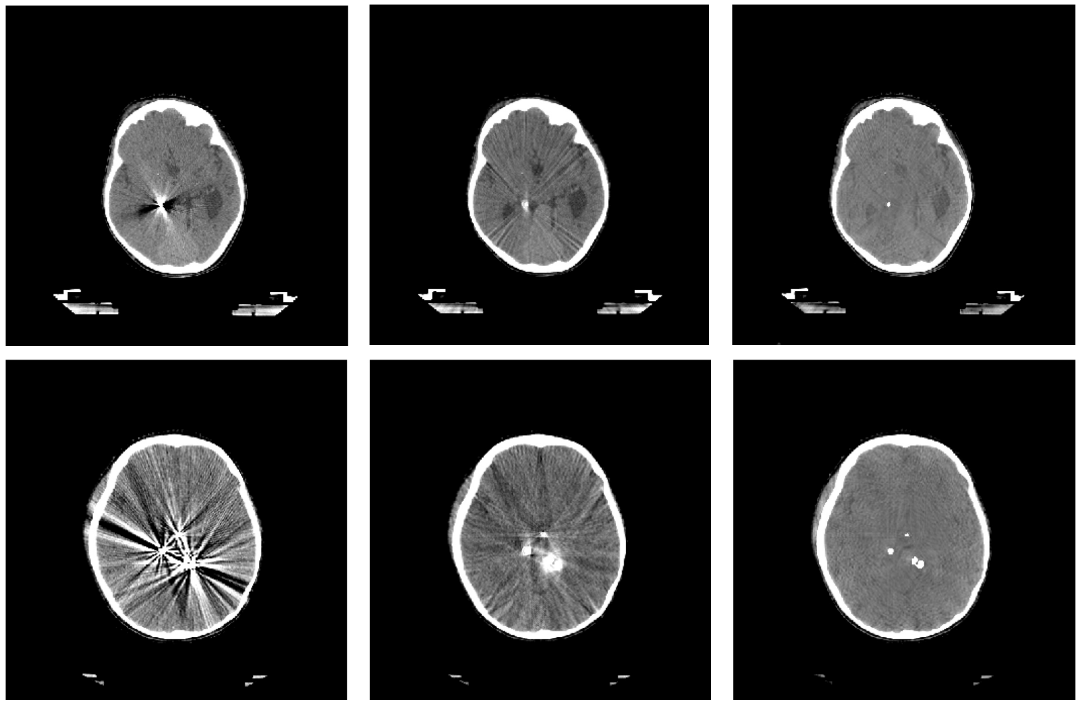

Embolic agents injected during the first stage of this treatment can be divided into solids (for example, metal coils) and liquids. Metal components of the embolic agents, as well as coils’ metal body, cause severe artifacts on CT scans, producing both bright regions of high absorption and dark regions of low absorption. Several studies have proposed that the presence of these high-density objects induces beam hardening artifacts on CT scans and might distort the dose calculation accuracy of the radiosurgery planning [6]. Figure 1 shows CT scans of two patient with AVMs after embolization (see more technical details on types of embolization in Section III-A).

Refer to caption

Figure 1: Liquid (left) and solid (right) embolization of the AVMs with notable artifacts on the CT images due to the metal components of the embolic materials.